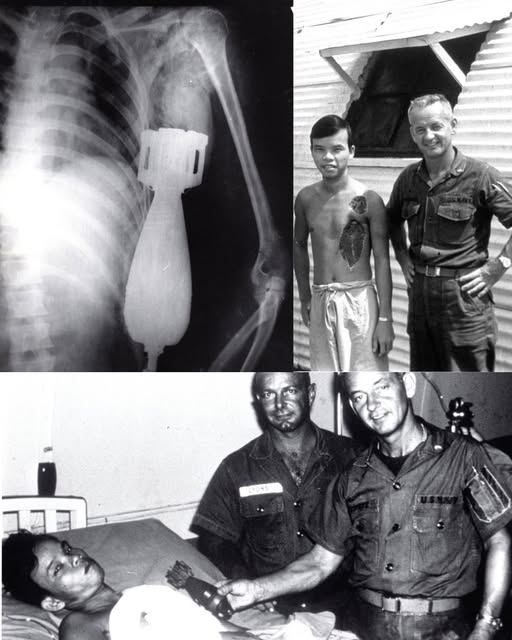

Pasien itu bernama Nguyen Van Luong, seorang prajurit Angkatan Darat Vietnam Selatan (ARVN). Dia masuk dengan napas tersengal, wajah pucat, dan lubang menganga di bahu. Namun, bukan lukanya yang membuat para perawat medis terdiam kaku.

Nguyen Van Luong selamat. Ia pulang bukan hanya dengan bekas luka jahitan, tapi dengan kisah tentang bagaimana musuh menanamkan kematian di dadanya, dan bagaimana sekumpulan orang asing bertaruh nyawa untuk mencabutnya.

- Dokter Utama: Commander Harry B. Witt, MC, USN (Chief of Surgery).